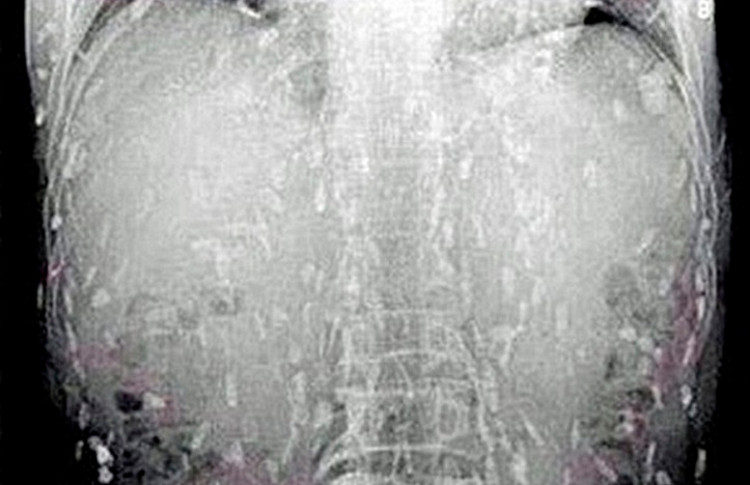

Aconteceu com um chinês que morreu após ingerir comida japonesa contaminada com vermes. O homem passou mal e foi parar no hospital após sentir muitas dores de estômago e coceira na pele. Ele passou por vários exames e os médicos descobriram que ele estava com o corpo cheio de lombrigas devido a grande quantidade de sashimi que ele havia comido nos últimos meses.